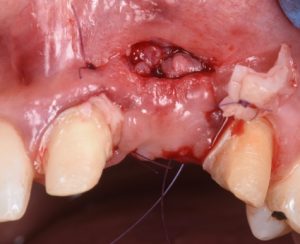

The procedure demonstrates the use of a horizontal vestibular incision with tunneling to mobilize the soft tissues and elevate the papillae. An autogenous connective tissue graft (CTG) harvested from the palate and maxillary tuberosity is utilized to augment tissue thickness. Additionally, a xenogenic bone graft is placed over the crestal area to serve as a space-maintaining scaffold and support vertical tissue stability.

Advanced flap advancement and suturing techniques are highlighted to ensure graft stability and optimal soft tissue outcomes.